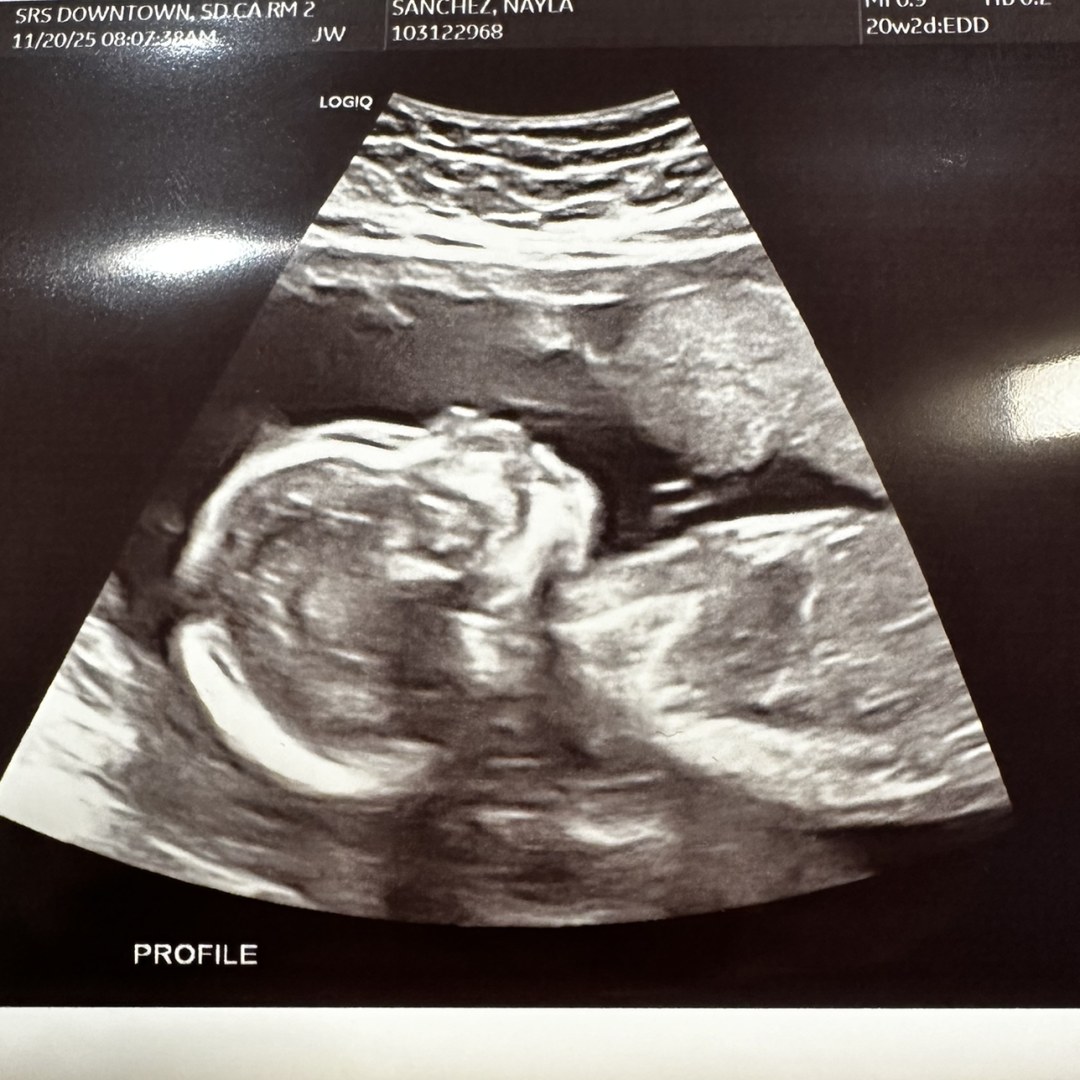

Nayla's Baby Registry

Nayla Sanchez & Izaac Gonzalez

San Diego, CA

April 7, 2026